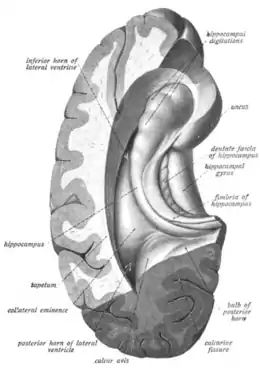

The hippocampus can be seen as a ridge of gray matter tissue, elevating from the floor of each lateral ventricle in the region of the inferior or temporal horn.[16][17] This ridge can also be seen as an inward fold of the archicortex into the medial temporal lobe.[18] The hippocampus can only be seen in dissections as it is concealed by the parahippocampal gyrus.[18][19] The cortex thins from six layers to the three or four layers that make up the hippocampus.[20]

The hippocampus, including the dentate gyrus, has the shape of a curved tube, which has been compared to a seahorse, and a ram's horn (Cornu Ammonis). Its abbreviation CA is used in naming the hippocampal subfields CA1, CA2, CA3, and CA4.[19] It can be distinguished as an area where the cortex narrows into a single layer of densely packed pyramidal neurons, which curl into a tight U shape. One edge of the "U," – CA4, is embedded into the backward-facing, flexed dentate gyrus. The hippocampus is described as having an anterior and posterior part (in primates) or a ventral and dorsal part in other animals. Both parts are of similar composition but belong to different neural circuits.[21] In the rat, the two hippocampi resemble a pair of bananas, joined at the stems by the commissure of fornix (also called the hippocampal commissure). In primates, the part of the hippocampus at the bottom, near the base of the temporal lobe, is much broader than the part at the top. This means that in cross-section the hippocampus can show a number of different shapes, depending on the angle and location of the cut.

In a cross-section of the hippocampus, including the dentate gyrus, several layers will be shown. The dentate gyrus has three layers of cells (or four if the hilus is included). The layers are from the outer in - the molecular layer, the inner molecular layer, the granular layer, and the hilus. The CA3 in the hippocampus proper has the following cell layers known as strata: lacunosum-moleculare, radiatum, lucidum, pyramidal, and oriens. CA2 and CA1 also have these layers except the lucidum stratum.